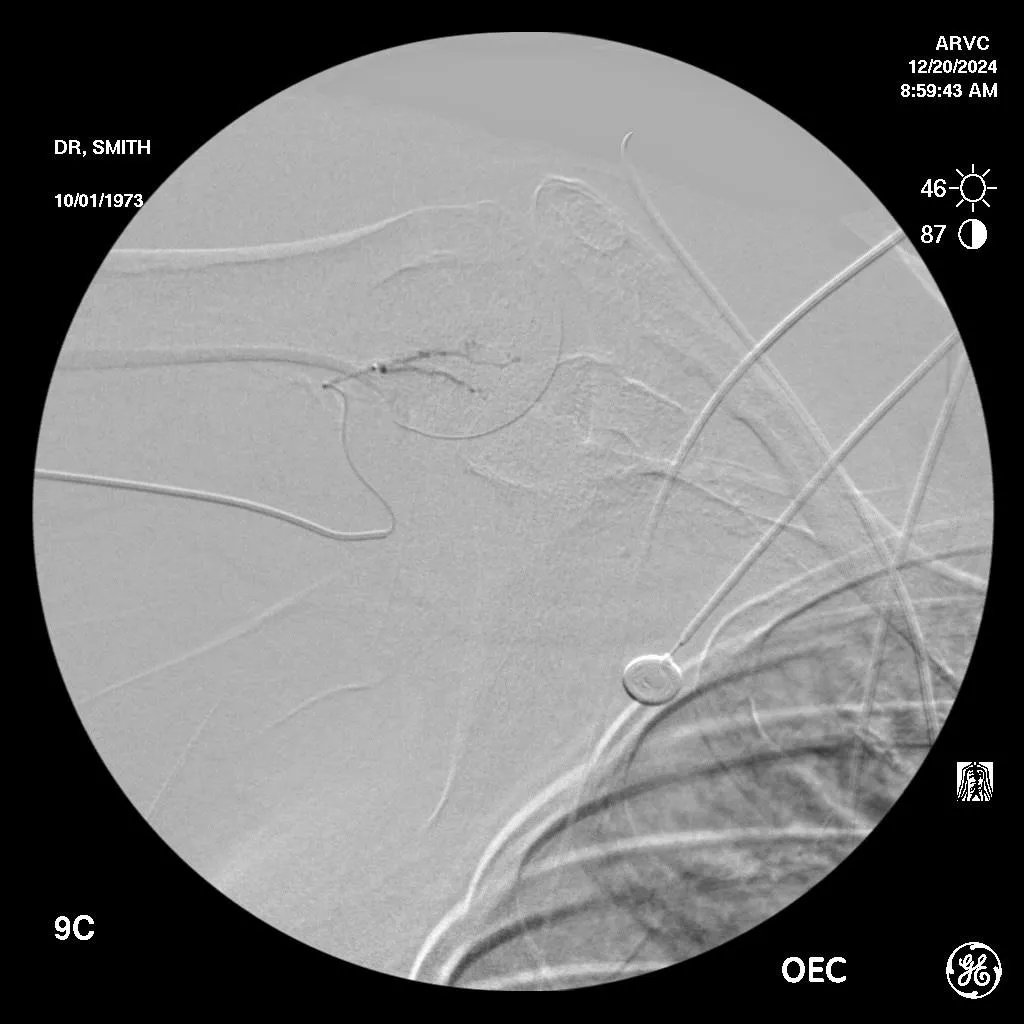

After embolization, the excessive hypervascularization "disappears" improving pain and function by eliminating the source of the inflammation.